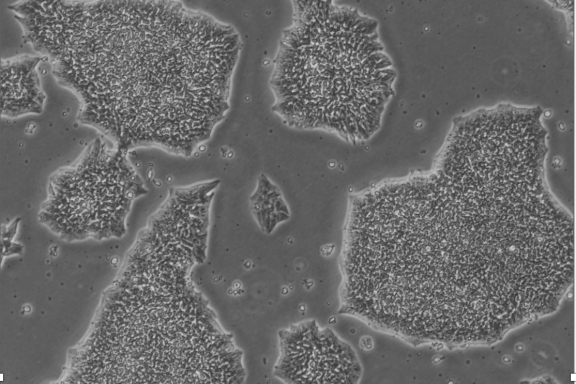

شیدا صادقی: با گسترش نگرانیها نسبت به استفاده از سلولهای بنیادی جنینی، محققان راهکارهایی برای کاهش این دغدغهها پیشنهاد دادهاند. از جمله این راهکارها، توسعه سلولهای بنیادی پرتوان القایی (iPSCs) است که از سلولهای سوماتیک افراد بالغ بهدست میآید و به جنین نیازی ندارد. این سلولها، ضمن حفظ ویژگیهای پرتوانی، مشکلات مربوط به رد ایمنی را نیز کاهش میدهند، زیرا از خود بیمار استخراج میشوند. هرچند در ادامه مشخص شد که این نوع سلولها ممکن است با بیثباتی ژنتیکی و احتمال تشکیل تومور همراه باشند، اما توسعه فناوریهای جدیدتر، مانند برنامهریزی جزئی و استفاده از سلولهای بنیادی خون بند ناف، مسیرهای ایمنتر و اخلاقیتری را فراهم کرده است

محدودیت دیگر، به توان تمایزی برخی از انواع سلولهای بنیادی برمیگردد. سلولهای بنیادی بالغ، مثل سلولهای مغز استخوان یا سلولهای خونی، فقط قادر به تولید نوع خاصی از سلولها هستند. این موضوع باعث میشود کاربرد آنها در برخی درمانها محدود شود. به همین دلیل، تحقیقات به سمت استفاده از سلولهای پرتوان القایی (iPSC) یا سلولهای جنینی رفته، اما این مسیر هم با پیچیدگیها و مسائل اخلاقی خاص خود همراه است.

سلولهای بنیادی، بهویژه از نوع جنینی، دارای خاصیت پرتوانی هستند که میتوانند به انواع مختلف سلولهای تخصصی تبدیل شوند. این ویژگیها میتوانند باعث تقسیم سلولی سریع و تکثیر بیش از حد شوند. به همین دلیل، اگر این سلولها بهدرستی مدیریت نشوند، امکان ایجاد سرطان یا جهش در آنها وجود دارد.

یکی از دلایل این مسئله، برهمکنش غیرطبیعی بین سلولهای بنیادی است. مطالعات نشان داده که اشتباه در انتقال پروتئینها، مانند پروتئینهای FGF، میتواند باعث بیدار شدن سلولهای بنیادی و آغاز تقسیمات غیرطبیعی آنها شود. این تکثیر غیرقابل کنترل میتواند منجر به تشکیل تومورها یا فعالسازی سلولهای سرطانی نهفتهای شود که از درمانهای رایج دور ماندهاند و در نهایت باعث عود بیماری و ایجاد متاستاز شوند. بنابراین، سلولهای بنیادی ممکن است بهعنوان محرکهایی برای بازگشت سلولهای سرطانی عمل کنند.